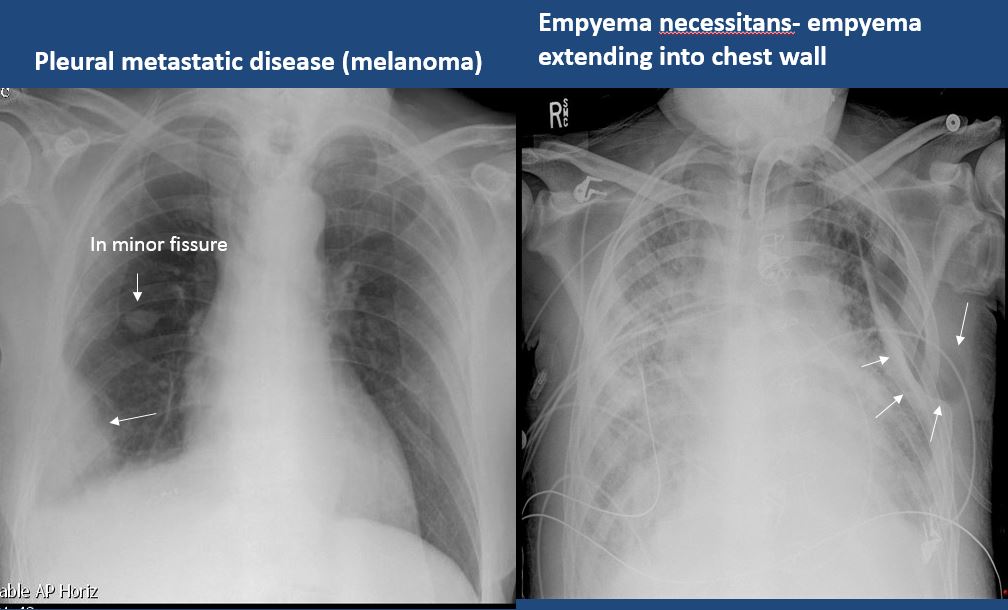

There is focal or diffuse abnormality of the pleura or chest wall. |

no | NA |

There is a pleural effusion or blunting of the costophrenic angle. |

Yes | NA |

There is focal fluid in the fissures. |